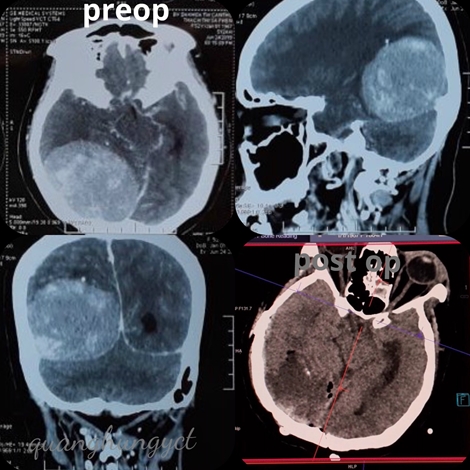

Cứu sống bệnh nhân bị u màng não "khủng"

12:55 01/07/2019

Ngày 1-7, Bệnh viện đa khoa Trung ương (BVĐKTƯ) Cần Thơ cho biết, các bác sĩ (BS) của BV vừa phẫu thuật thành công u màng não "khủng" cho một bệnh nhân. Đây là trường hợp đầu tiên được thực hiện tắc mạch trước khi mổ lấy u màng não.